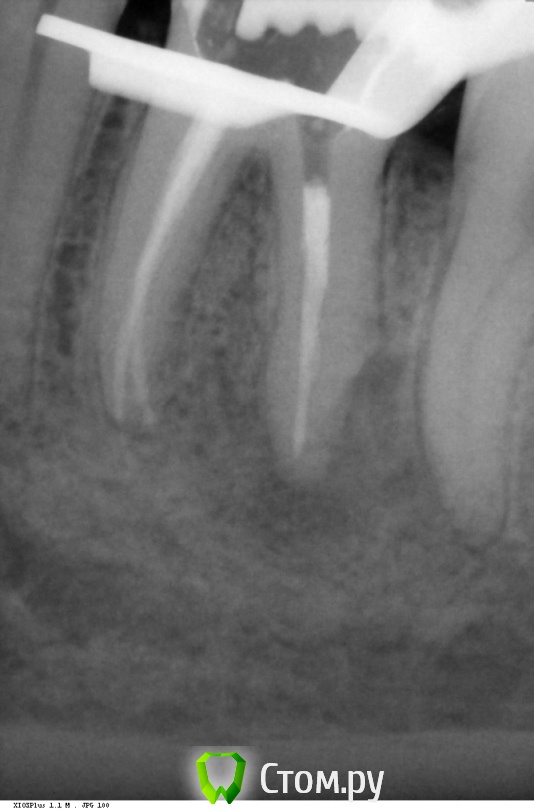

arimo Опубликовано 11 декабря, 2013 Поделиться Опубликовано 11 декабря, 2013 Добрый день. Помогите понять что дальше делать с зубом.Зуб- нижняя левая шестерка, депульпирован около 10 лет назад, периодически ныл, потом все проходило. В конце сентября начались сильные боли, неделю пришлось принимать кетанов. Врач вскрыл каналы (был гной), промыл, положил лекарство (какой то препарат кальция), через 2 недели запломбировал.Через 10 дней началась боли при надкусывании. Сейчас зуб сильно ноет, чувство распирания в десне, боль при легком касании.Вопросы:1. Имеет смысл повторно вскрывать каналы и класть лекарство?2. Если нет, имеет ли смысл делать резекцию корня и какие могут быть последствия? Ссылка на комментарий